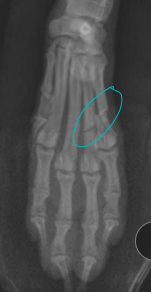

Carpal, Metacarpal, Digital, Metatarsal Fractures

Very common, greyhounds

Carpal: lag screw

Metacarpal and Metatarsal: medical tx most common

Tx: closed reduction + caudal splint (Rx #1), IM pins/plates + caudal splint (Sx)

Sx indicated if open, grossly displaced, intra-articular, or all 4 fractured

Digital: caudal splint bandage for 6w